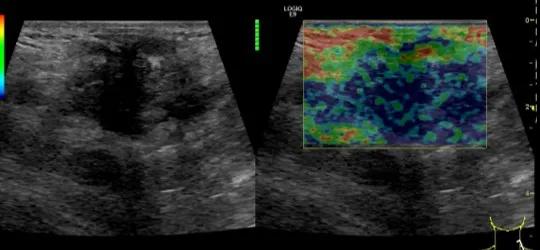

第二例是食管癌患者,术后半年余锁骨上固定淋巴结可触及肿大,疼痛非常明显,系统治疗后无缓解,患者希望通过局部处理缓解症状。造影显示强化信号明显,结节部分区域坏死,故主要针对强化区域从后向前的逐层的消融,皮下进行液体隔离减少烫伤。热消融后影像显示血流增强消失,弹性、硬度增高,一个月后复查显示充盈缺损,完全消融,疗效远超预期。

(病例2图例)